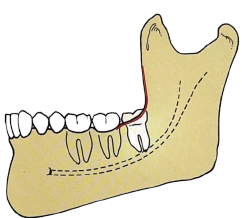

A classificação de Pell e Gregory é um método utilizado para classificar os terceiros molares impactados baseado na quantidade do dente impactado que está coberto com o osso do ramo mandibular.

Analise a imagem a seguir:

De acordo com a classificação de Pell e Gregory, a imagem refere-se a uma impactação: